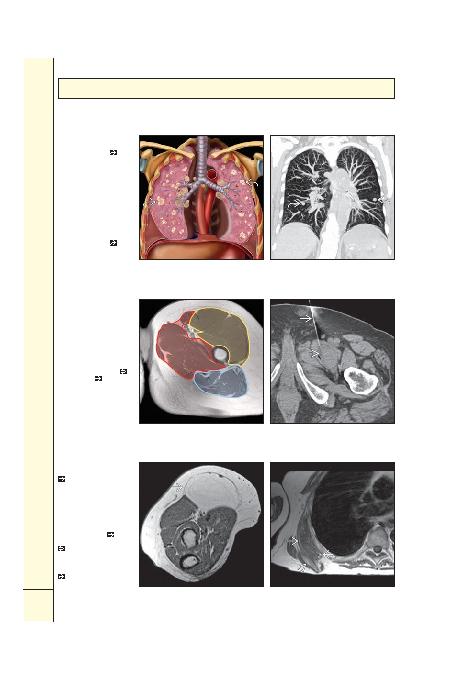

Sol) Akcierlerden geçen

koronal grafik bilateral

metastazlari gösteriyor

.

Uzak metastazlarin varlii evre

IV hastalia iaret eder. Evre IV

primer sarkomlar herhangi bir

boyutu, herhangi bir derinlik

ve herhangi bir histolojik

derecede olabilir. Yumuak

doku sarkomu metastazlarinin

%75'inden fazlasi akcieredir.

(Sa) Koronal kontrastli

BT (MIP) uylukta yüksek

dereceli liposarkomu olan bir

hastada bilateral pulmoner

. Uzak metastazlarin varlii

hastalii evre IV (T2b N0 M1

G3) yapar.

(Sol) Aksiyel grafik uyluk

üst bölümündeki kas

kompartmanlarini farkli

renklerde gösteriyor.

Yumuak doku kitlesine

biyopsi yapilirken komu kas

bölmelerine bula olmamasi

önemlidir, bula durumunda

daha geni rezeksiyon gerekir.

(Sa) Aksiyel kontrastsiz BT

pektineus kasindaki kitleye

ine biyopsisini

gösteriyor.

Bu kitle siviya duyarli

sekanslarda aliilmiin diinda

düük sinyalli idi. Biyopsi

desmoplastik fibrom geldi.

(Sol) Ön kol aksiyel T1 A

MR benign lipomu gösteriyor

. Kitle cilt alti ya ile

ayni sinyalde, nodül ya da

kalin septa içermemekte.

Hatta kitleyi ince bir kapsül

çevreliyor. Bu kitle fizik

muayenede arili ve gergindi.

(Sa) Aksiyel T1 A MR kasla

neredeyse izointens bir

göüs duvari kitlesini

gösteriyor. Burasi skapulanin

alt ucu ile göüs kafesi

arasinda elastofibromun klasik

yerleimidir. Kitle küçük,

yüksek sinyalli ya odaklari

içerir.